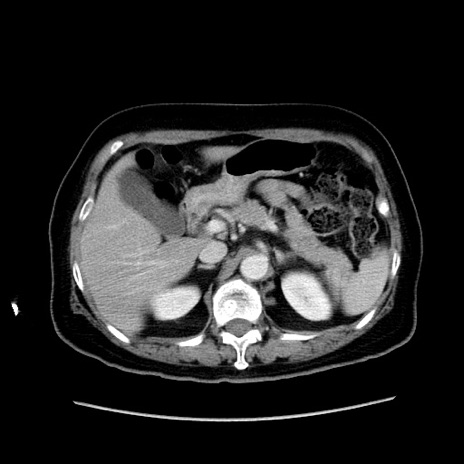

冠状断像

【症例】80歳代女性

【主訴】下腹部痛

【現病歴】約8時間前より下腹部痛の出現あり、救急外来受診。

【既往歴】両側付属器切除

【身体所見】意識清明、下腹部正中に手術痕あり、その部位に一致して圧痛と反跳痛あり。腸蠕動音は亢進。

【データ】WBC 9300、CRP 0.15